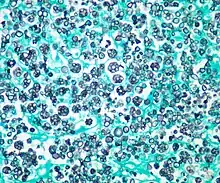

| Histologic stain of a Prototheca zopfii infection in a dog | |

Protothecosis, otherwise known as Algaemia, is a disease found in dogs, cats, cattle, and humans caused by a type of green alga known as Prototheca that lacks chlorophyll and enters the human or animal bloodstream. It and its close relative Helicosporidium are unusual in that they are actually green algae that have become parasites.[1] The two most common species are Prototheca wickerhamii and Prototheca zopfii. Both are known to cause disease in dogs, while most human cases are caused by P. wickerhami.[2] Prototheca is found worldwide in sewage and soil. Infection is rare despite high exposure, and can be related to a defective immune system.[3] In dogs, females and Collies are most commonly affected.[4]

Prototheca has been thought to be a mutant of Chlorella, a type of single-celled green alga. However, while Chlorella contains galactose and galactosamine in the cell wall, Prototheca lacks these. Also, Chlorella obtains its energy through photosynthesis, while Prototheca is saprotrophic, feeding on dead and decaying organic matter. When Prototheca was first isolated from slime flux of trees in 1894, it was thought to be a type of fungus.[6] Its size varies from 2 to 15 micrometres.[7]

In dogs

Disseminated protothecosis is most commonly seen in dogs. The algae enters the body through the mouth or nose and causes infection in the intestines. From there it can spread to the eye, brain, and kidneys. Symptoms can include diarrhea, weight loss, weakness, inflammation of the eye (uveitis), retinal detachment, ataxia, and seizures.[11]

Dogs with acute blindness and diarrhea that develop exudative retinal detachment should be assessed for protothecosis.[6] Diagnosis is through culture or finding the organism in a biopsy, cerebrospinal fluid, vitreous humour, or urine. Treatment of the disseminated form in dogs is very difficult, although use of antifungal medication has been successful in a few cases.[4] Prognosis for cutaneous protothecosis is guarded and depends on the surgical options. Prognosis for the disseminated form is grave. This may be due to delayed recognition and treatment.[3]